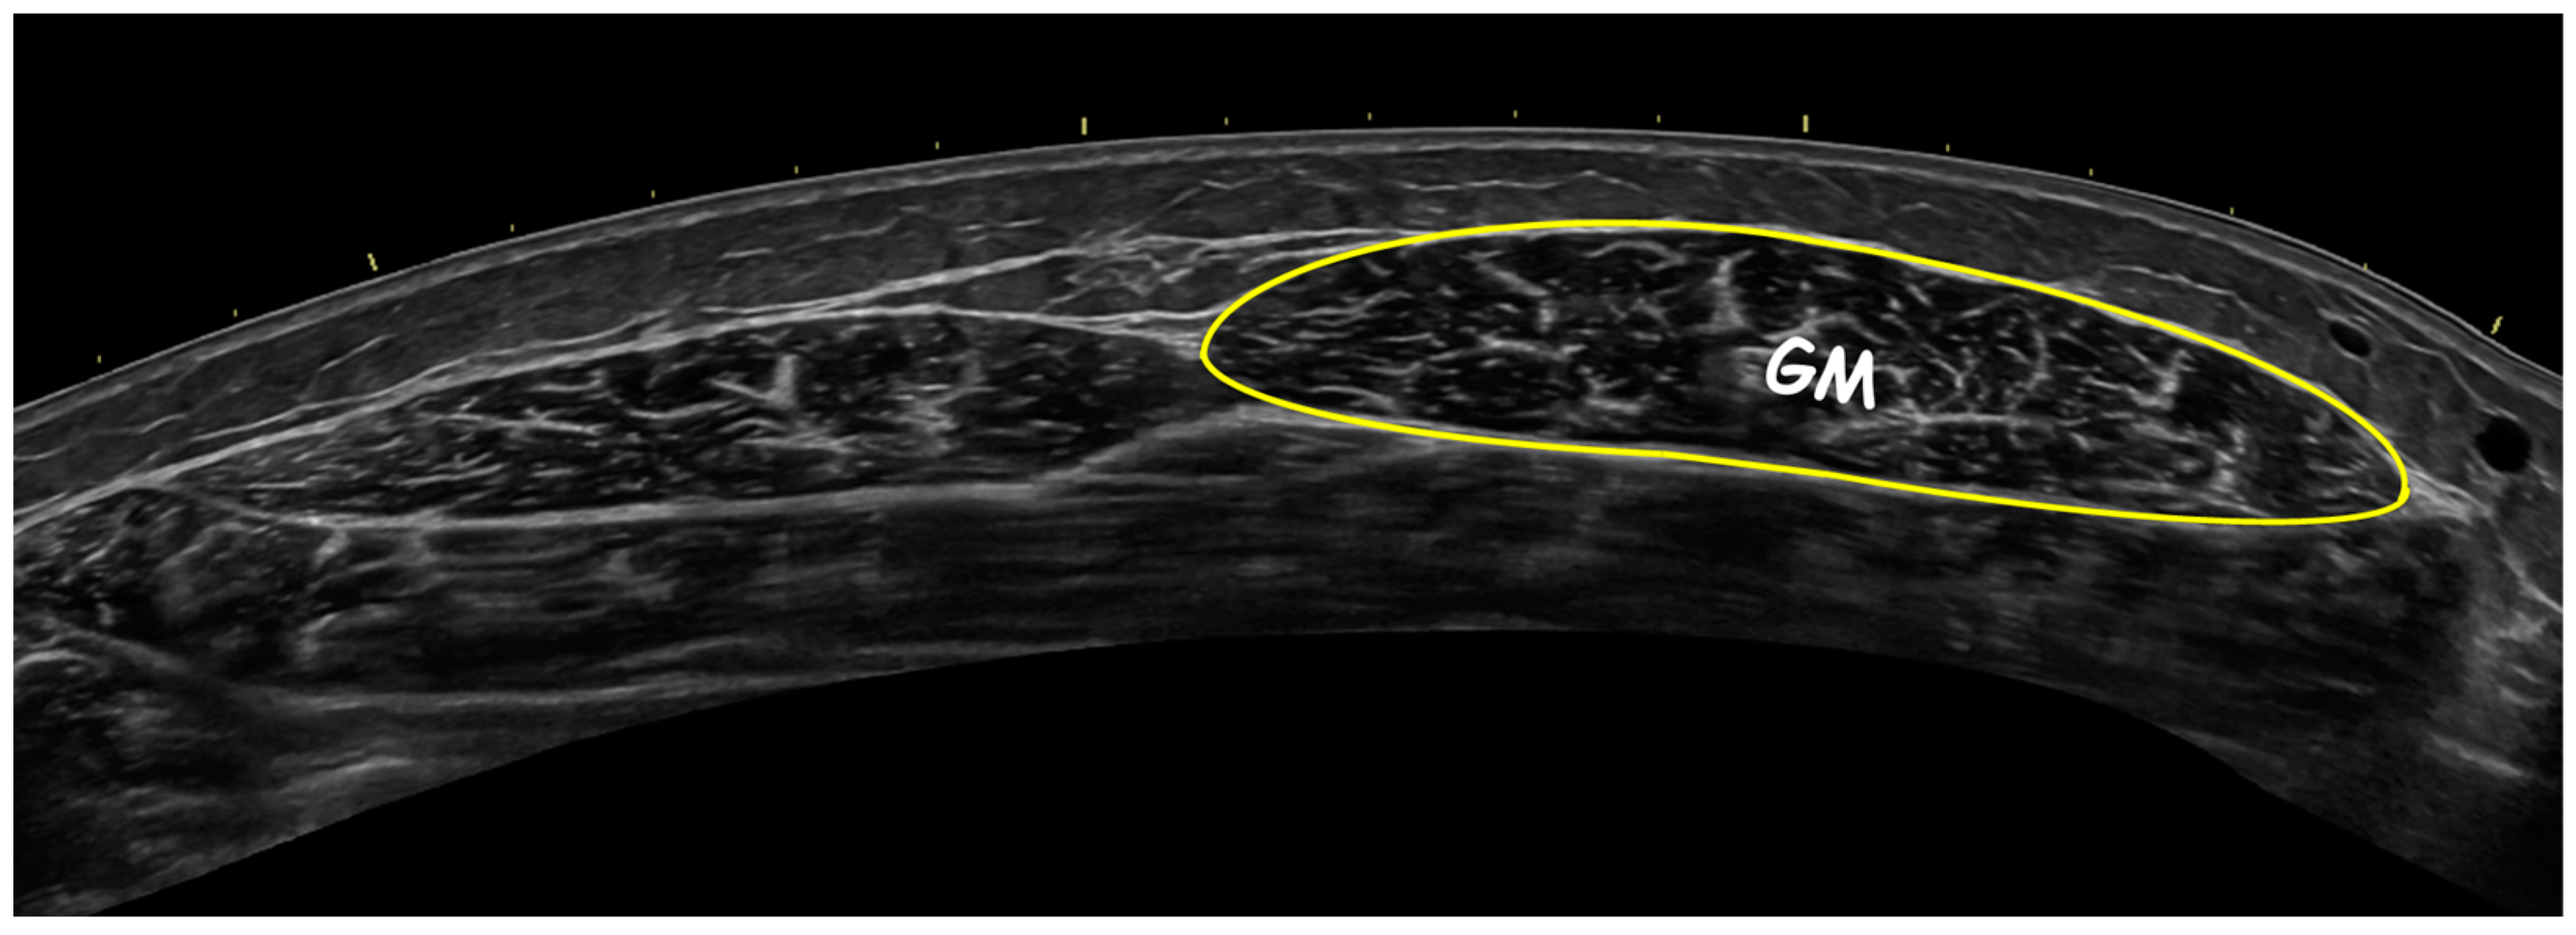

2.4. Ultrasonography